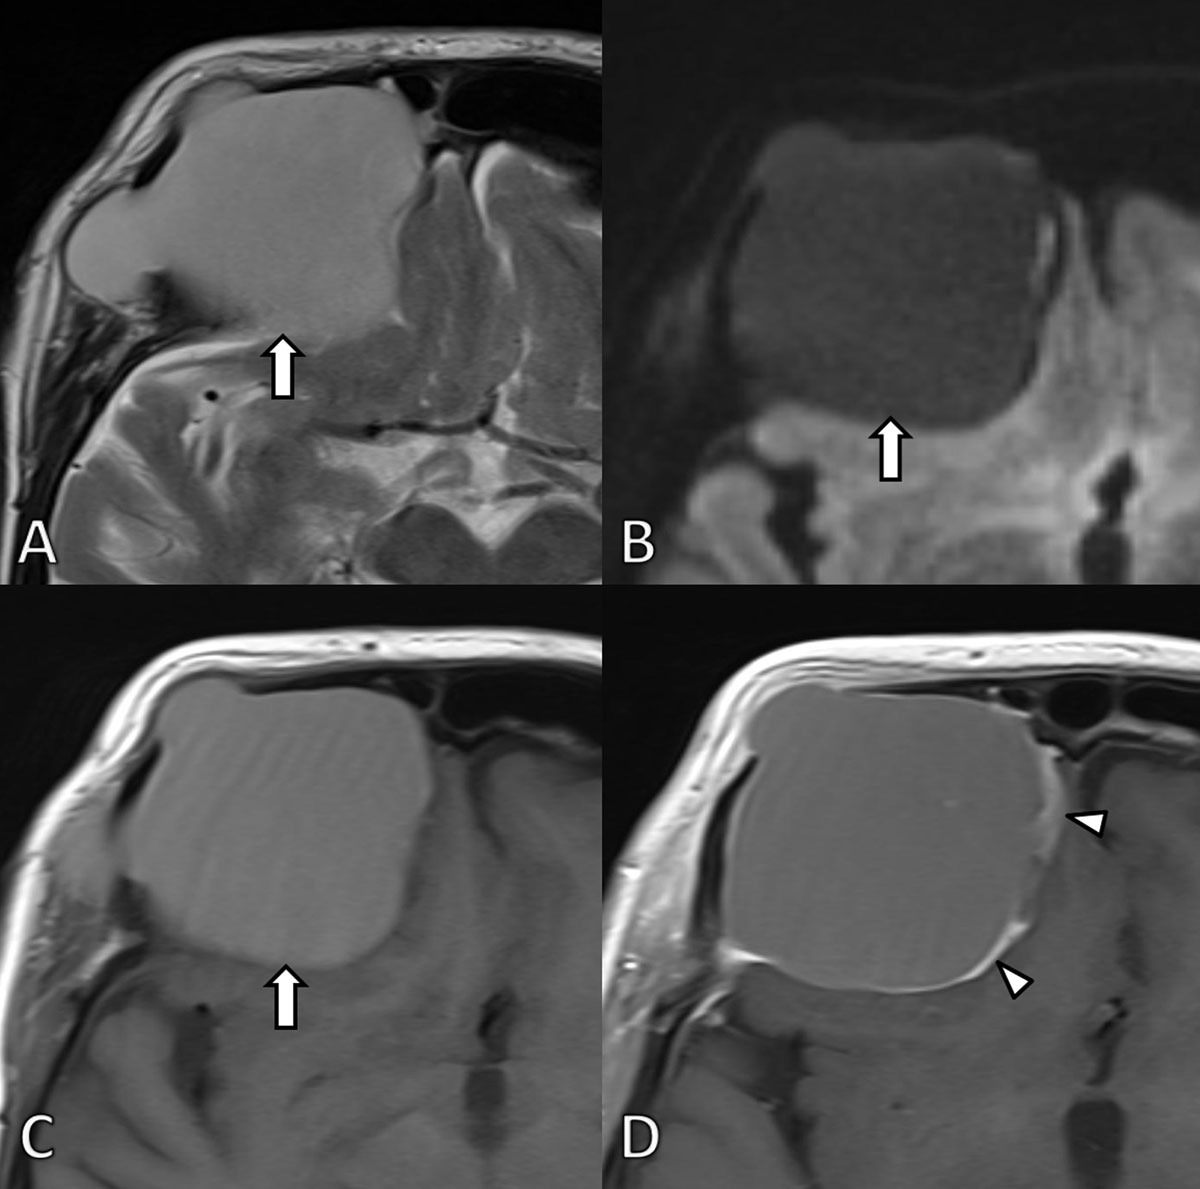

Figure 2

MRI at first admission. A. Axial T2-WI. B. Diffusion weighted image (b1000) and C. T1-WI before and D. after gadolinium contrast administration confirm the presence of a well-defined expansile mass (arrow) at the frontal bone. The signal is homogenously hyperintense on T2 and T1-WI images in keeping with high protein content. The lesion did not demonstrate restricted diffusion. After administration of gadolinium contrast the lesion shows subtle peripheral contrast enhancement (arrowheads). The lesion exerts mass effect on the frontal lobe.